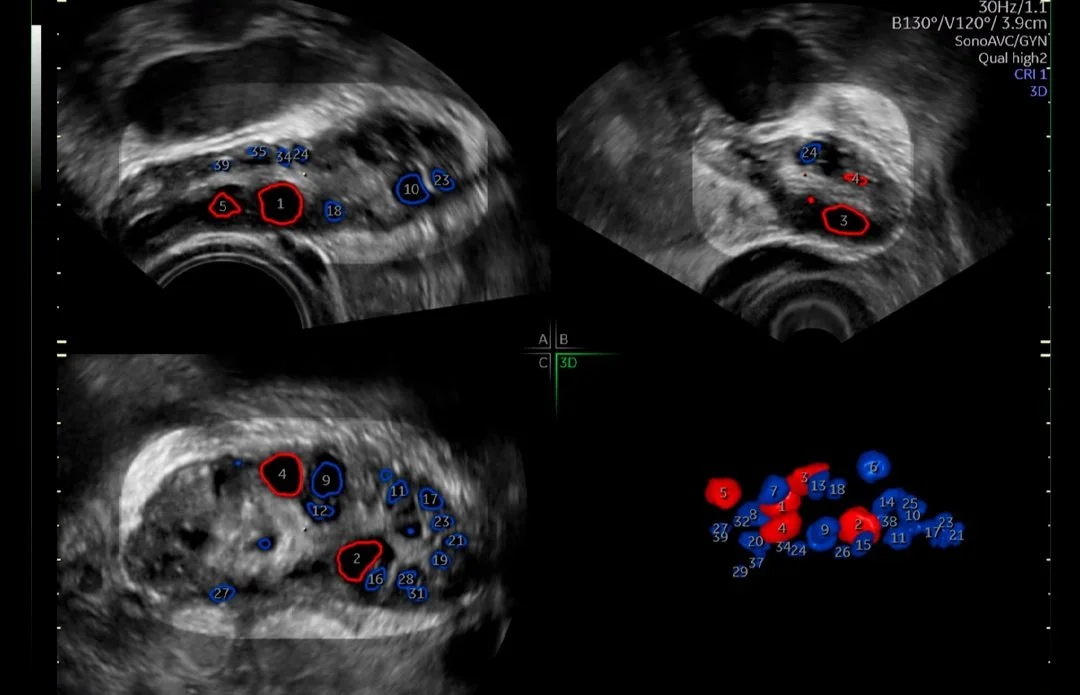

Medicina reproductiva asistida

Entendemos el impacto que tiene la infertilidad en la vida de sus pacientes y en su práctica. Por este motivo, los sistemas de ultrasonidos Voluson superan continuamente los límites de la adquisición de imágenes para ofrecerle herramientas sencillas e innovadoras que le ayuden a usted y a sus pacientes a vivir el sueño de un embarazo próspero.